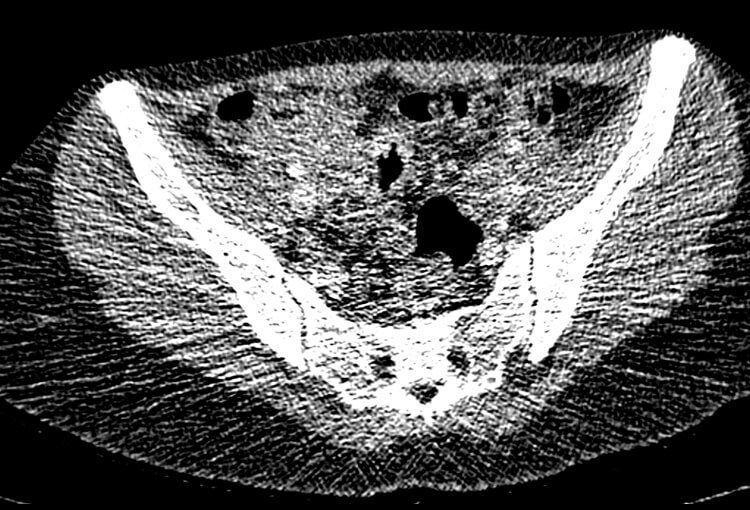

120 kV / 20 mAs / 1 mm

Before FBP (Noise 189) VS After ClariCT.AI (Noise 46) 76% Denoising